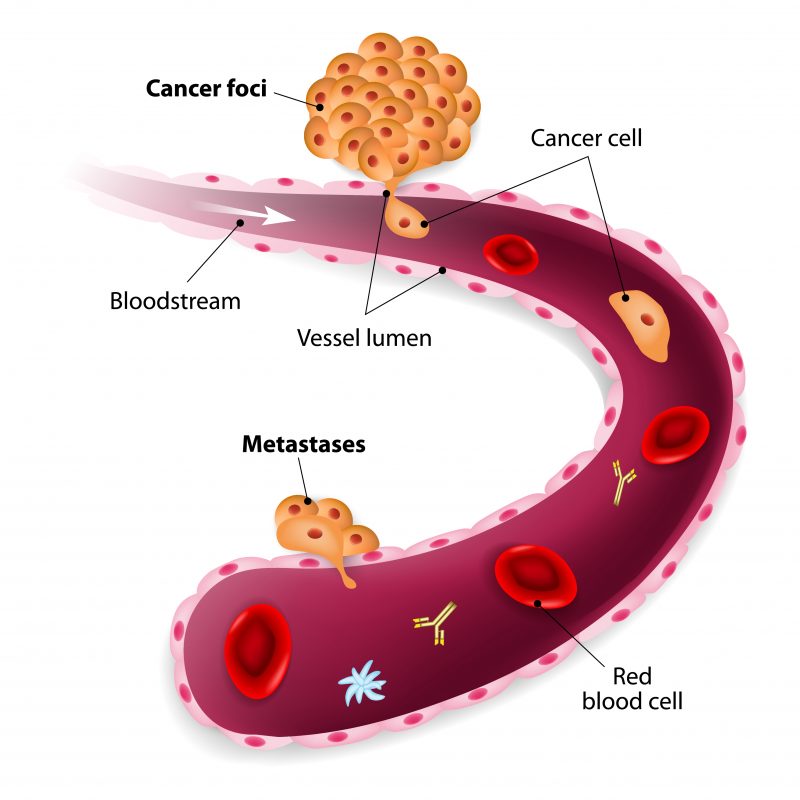

The Spread of Prostate Cancer – Prostate Cancer Research Centre